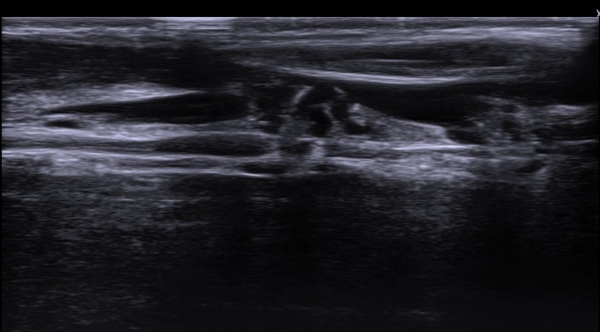

Å½ÃËÀÚ¸¦ Á¶±Ý ¸»´ÜÀ¸·Î À̵¿ÇÏ´Ï ±ÙÀ°ÇǺνŰæÀÇ À§ÃàÀÌ °üÂûµÇ°í(»çÁø 2) ŽÃËÀÚ¸¦ Á¶±Ý ´õ

¸»´ÜÀ¸·Î À̵¿ÇÏ´Ï ±ÙÀ°ÇǺνŰæÀÌ Á¤»êÀûÀ¸·Î °üÂûµÈ´Ù(»çÁø 3).